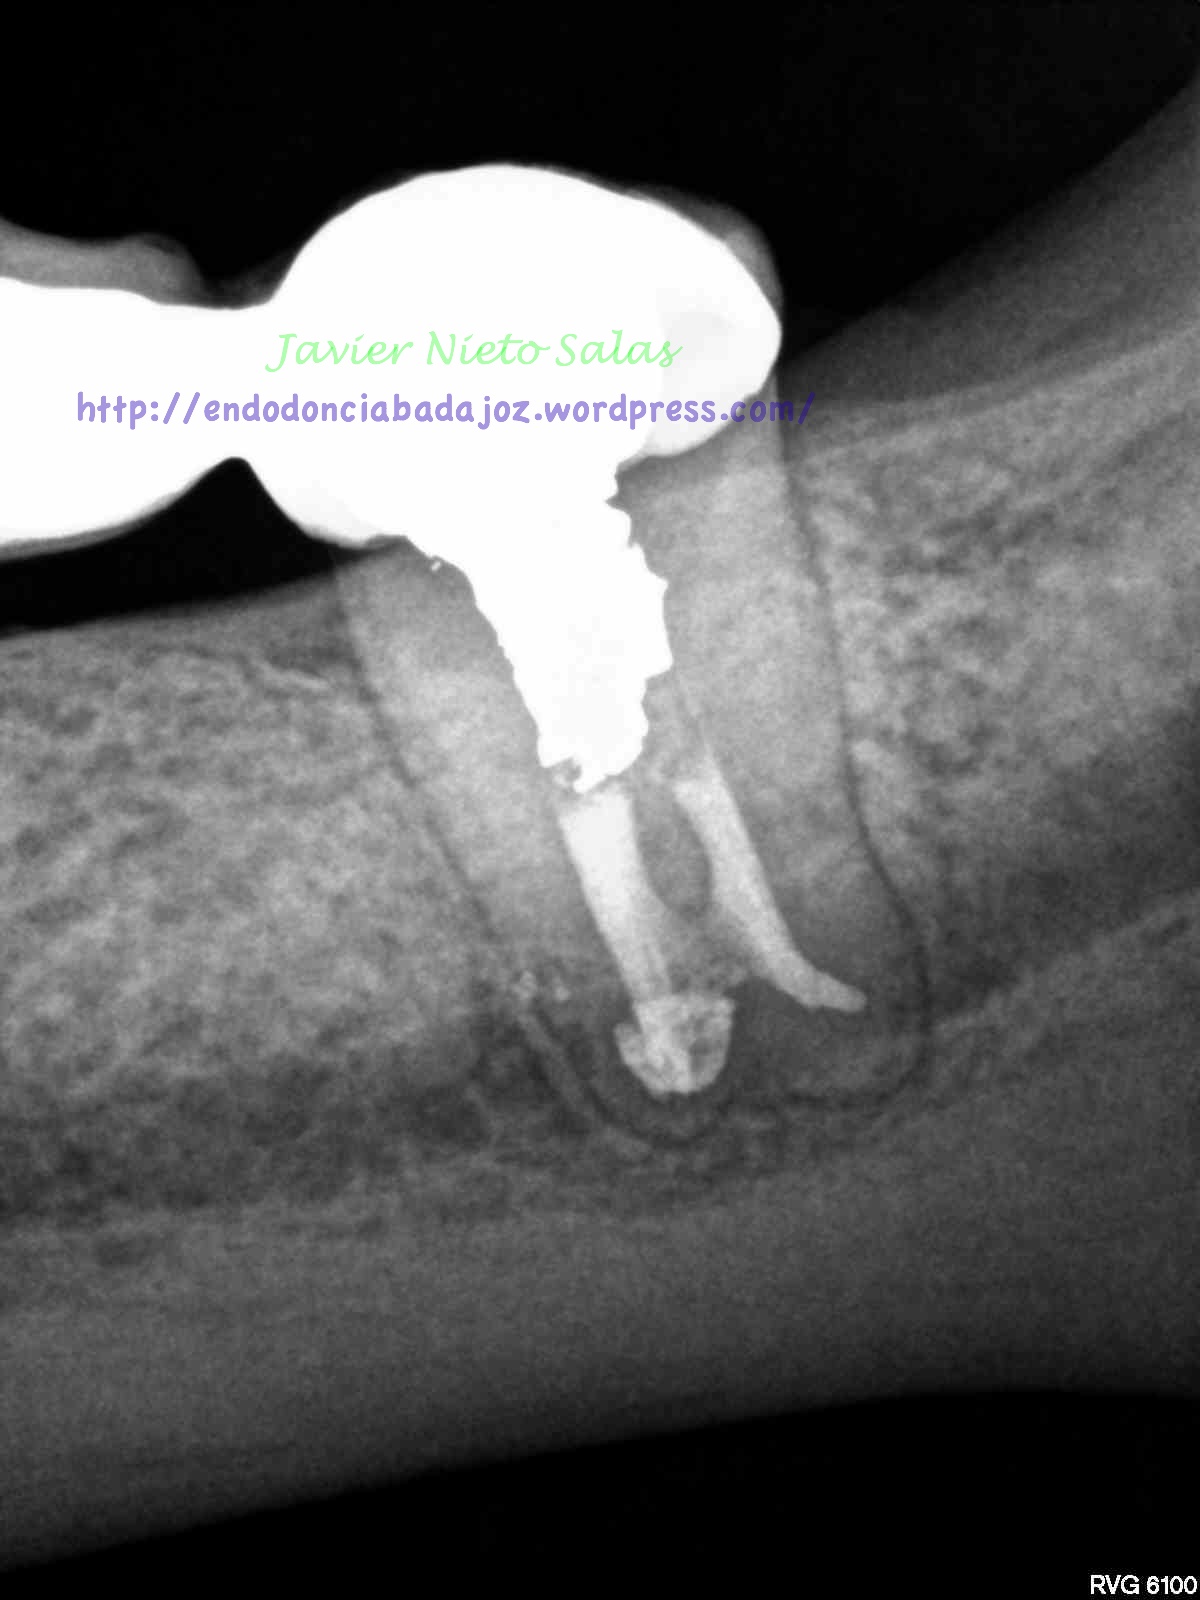

Nos llega un nuevo caso a revisión, pieza 3.7 endodociada por una periodontitis apical crónica, se trata de un conducto en «C», como ya hemos hablado en alguna entrada anterior, son sistemas de conductos complicados por la anastomosis de los conductos y la dificultad del sellado hermético y tridimensional de los mismos.

Pero el caso de hoy, no lo cuelgo por su dificultad, lo hago por varios motivos; el primero será el diagnóstico del caso, sólo radiograficamente, en este caso falta información, se puede sospecha de fractura vertical, por varios puntos, se trata de un segundo molar inferior, con un puente desde hace varios años, por la forma de la imagen de la lesión y el sondaje puntual. Pero como es sabido, el problema que tiene una «fractura vertical» es que todos esos signos coinciden con que puede tratarse de un «periodontitis apical crónica», como es el caso.

Pero cual es mi sorpresa y mi tristeza al ver la revisión del caso a los 9 meses. Filtración coronal con gran destrucción de la pieza, muy mal pronóstico.